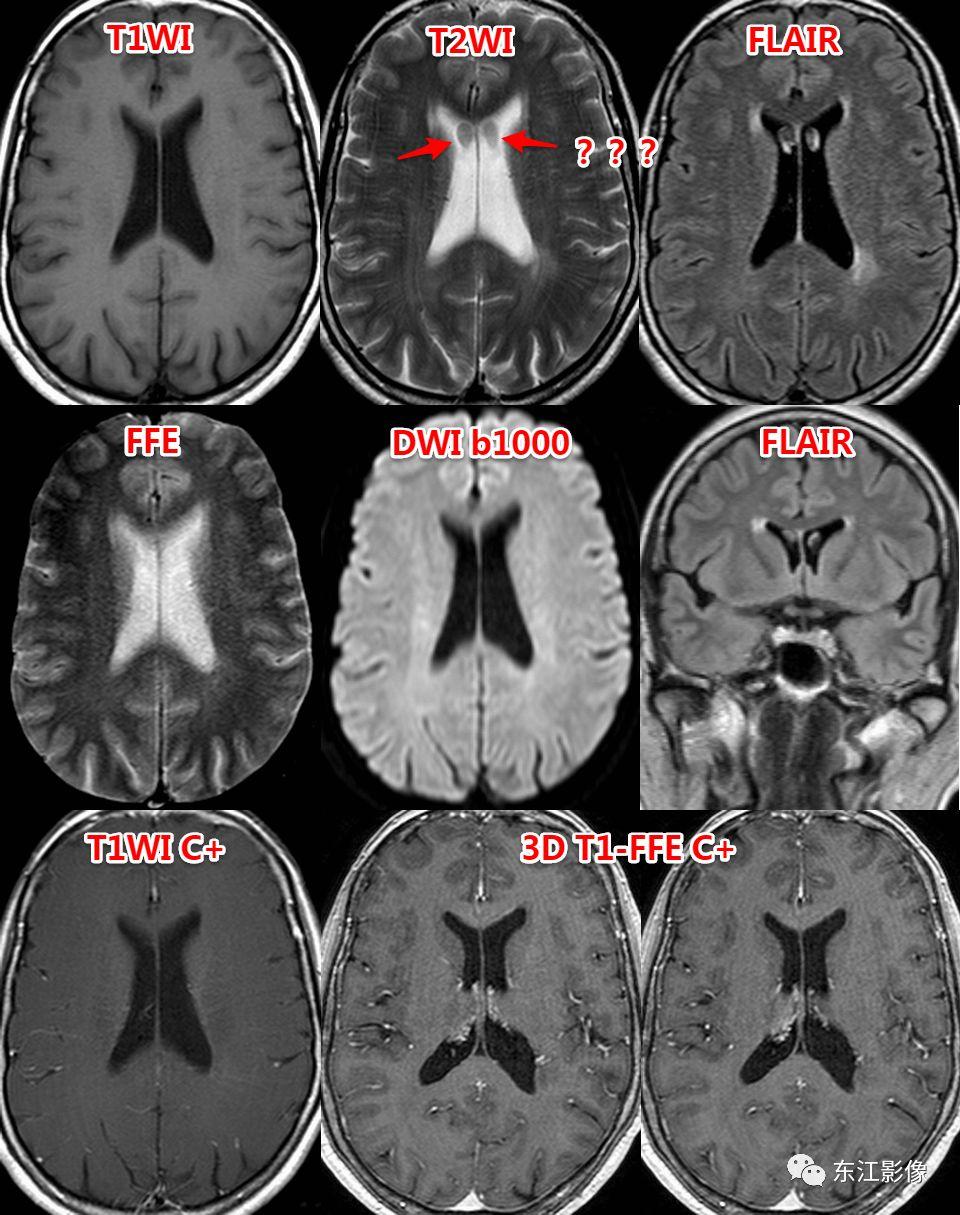

5. 脑脊液流动伪影

- 脑脊液流动伪影主要见于T2WI、FLAIR,主要是长TE序列容易出现流空效应的缘故。

- 但由于脑脊液流动方向、速率不一等因素的影响,呈现为非脑脊液信号影像,部分呈囊样。

- 常见于第三脑室、侧脑室室间孔旁区、脑干周围脑池(这些区域结构复杂)。

- 鉴别要点,T1WI、增强未能辨认;DWI与邻近一致的无信号;无占位效应。

侧脑室室间孔旁脑脊液流动伪影。

又一例。